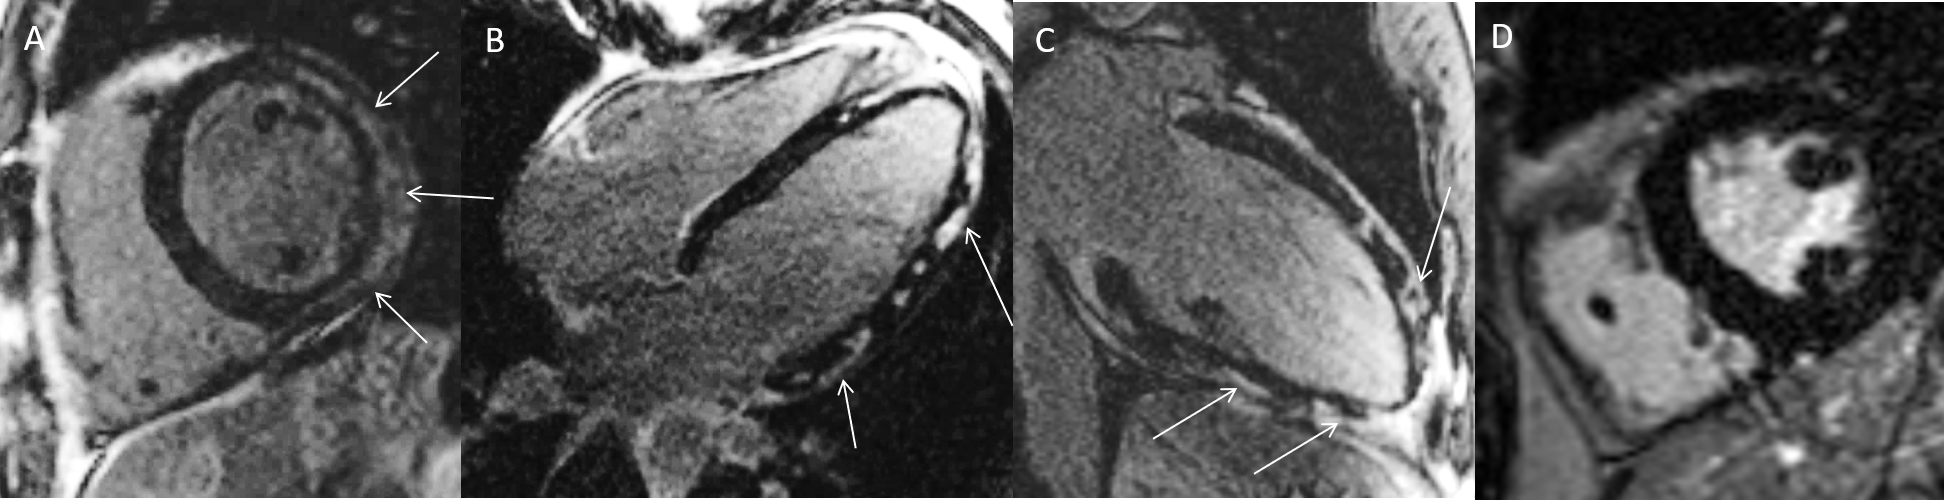

44-jährige Patientin mit stattgehabtem Infekt der oberen Atemwege und Brustschmerzen. Bei erhöhten Herzenzymen Durchführung einer Herzkatheteruntersuchung, welche keine Engstellen zeigen konnte. Im CMR kein Nachweis eines LGE (A), allerdings erhöhtes natives T1 (1180ms, Norm: <990ms) [B] sowie erhöhtes T2 (64ms, Norm: <50ms) [C] als Hinweis auf Myokarditis ohne fokale Narbenbildung. Die neueren Mapping-Verfahren erlauben den Nachweis einer diffusen Herzschädigung, wobei erhöhte T1-Werte vor allem narbige Veränderungen, und erhöhte T2-Werte akut-entzündliche Prozesse anzeigen können. Beide Prozesse können im Rahmen einer Myokarditis auftreten.